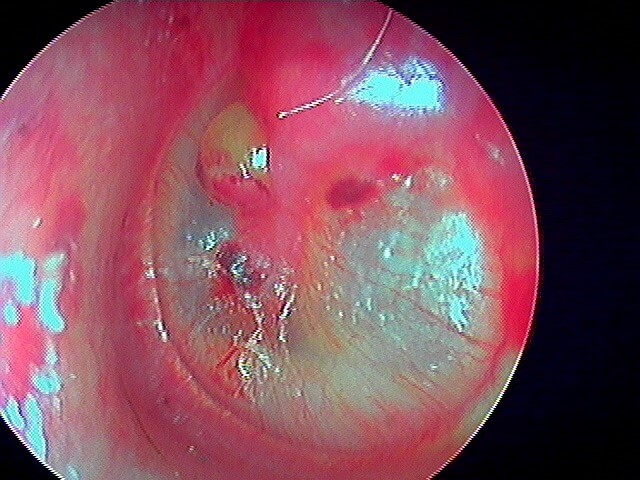

7 MYRINGOSCLÉROSE (ou TYMPANOSCLÉROSE)

Surcharge calcaire de la couche conjonctive tympanique: AUCUNE conséquence anatomique ou fonctionnelle (auditive), gêne parfois en cas de tympanoplastie. On parle plus de tympanosclérose quand ces plaques de calcaires (issues d'infections antérieures cicatrisées) sont dans la caisse; et de myringosclérose quand elles ne touchent que le tympan. En les voyant cela vous permettra d'affirmer que le patient·e a eu des otites dans l'enfance et puis c'est tout! Ces plaques sont superficielles et le tympan est normal, à ne pas confondre avec un cholestéatome.